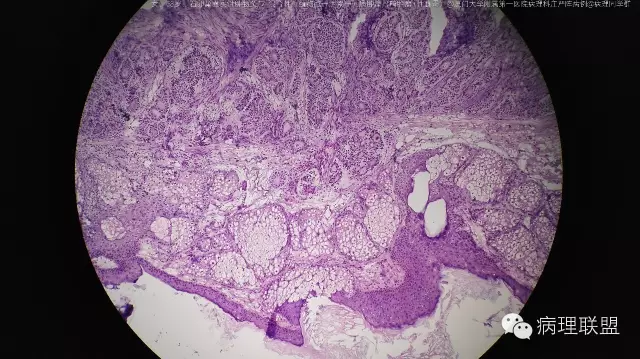

右卵巢囊实性肿物头节-混合性生殖细胞一性索一间质肿瘤(畸胎瘤+性腺母)